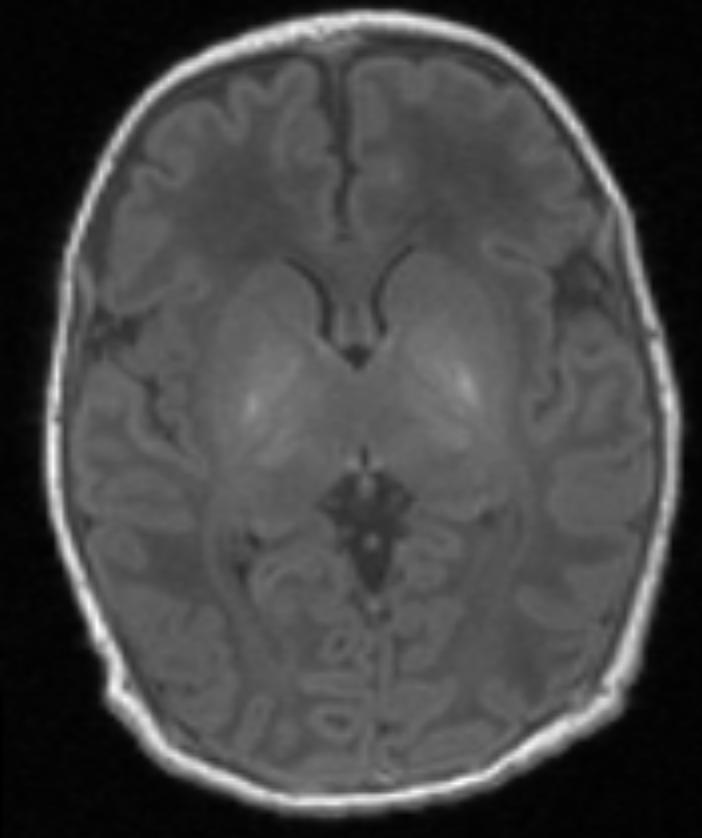

Scan one shows the brain of a healthy baby, while scan two shows that of a baby with brain damage. Compared to scan one, scan two shows abnormal brightness in the deep nuclei (in the centre of the brain), which indicates damage.